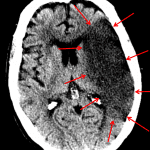

- Hypoattenuation throughout the left MCA territory with loss of gray-white differentiation and sulcal effacement

- Slight left to right midline shift without evidence of herniation

- Asymmetric increased density of the left carotid terminus and proximal left M1 segment

- Left MCA territory infarct

Hypoattenuation throughout the left MCA territory with loss of gray-white differentiation and sulcal effacement, compatible with early subacute ischemia. Slight left to right midline shift without evidence of herniation. No evidence of hemorrhagic transformation.

Asymmetric increased density of the left carotid terminus and proximal left M1 segment, likely representing thrombus.

- The MCA territory is by far the most common affected by ischemia

- The deep gray structures and insular cortex develop cytotoxic edema quicker (usually within a few hours) than the frontal, temporal, and parietal cortical gray matter because there is more developed surface cortex collateral flow, so look closely at the basal ganglia and insular cortex (e.g. insular ribbon sign, which is loss of gray-white differentiation between the insular cortex and external capsule)

- The earliest CT finding of MCA territory ischemia is a dense MCA sign (seen immediately), though this is seen in a minority of cases

- Always talk about mass effect (e.g. midline shift, herniation, hydrocephalus) and hemorrhagic conversion.